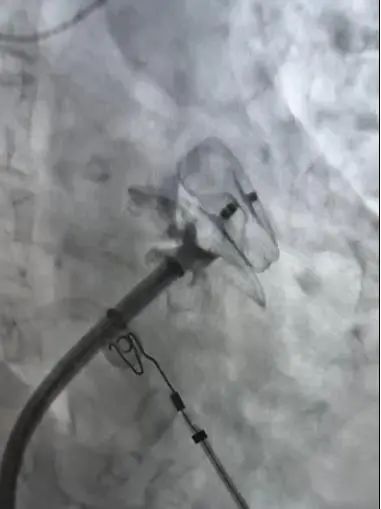

术中进行房颤环肺静脉隔离

手术在西安交通大学第二附属医院王洪涛教授的指导、何丽团队及超声科罗利红主任团队、相关科室的配合下开展。在确认患者心耳内无血栓的情况下,手术团队结合食道超声和CTPV术前结果,在完成环肺静脉隔离后,选择合适左心耳封堵器,一次展开即完成封堵,两种术式实现无缝衔接,手术用时约2个钟头。在医务人员的精心照护下,患者目前恢复良好。